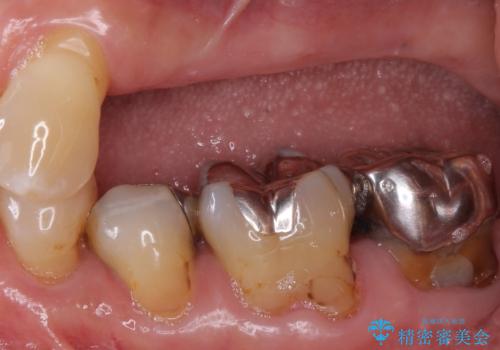

精査したところ右下の奥歯も歯周病により保存不可能な状態でした。

なるべく予算を抑えたいとのご希望から、上顎は入れ歯、右下臼歯部はインプラントによる治療を行いました。

インプラントの種類:スプラインツイスト